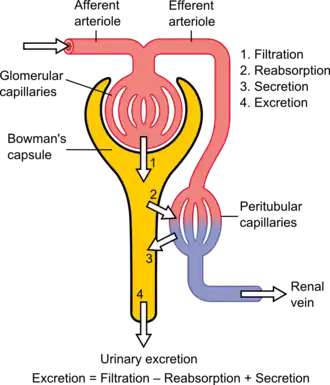

The kidneys excrete a variety of waste products produced by metabolism into the urine. The microscopic structural and functional unit of the kidney is the nephron. It processes the blood supplied to it via filtration, reabsorption, secretion and excretion; the consequence of those processes is the production of urine. These include the nitrogenous wastes urea, from protein catabolism, and uric acid, from nucleic acid metabolism. The ability of mammals and some birds to concentrate wastes into a volume of urine much smaller than the volume of blood from which the wastes were extracted is dependent on an elaborate countercurrent multiplication mechanism. This requires several independent nephron characteristics to operate: a tight hairpin configuration of the tubules, water and ion permeability in the descending limb of the loop, water impermeability in the ascending loop, and active ion transport out of most of the ascending limb. In addition, passive countercurrent exchange by the vessels carrying the blood supply to the nephron is essential for enabling this function.

Filtration

Filtration, which takes place at the renal corpuscle, is the process by which cells and large proteins are retained while materials of smaller molecular weights are[30] filtered from the blood to make an ultrafiltrate that eventually becomes urine. The adult human kidney generates approximately 180 liters of filtrate a day, most of which is reabsorbed.[31] The normal range for a twenty four hour urine volume collection is 800 to 2,000 milliliters per day.[32] The process is also known as hydrostatic filtration due to the hydrostatic pressure exerted on the capillary walls.

Reabsorption

Secretion

Secretion is the reverse of reabsorption: molecules are transported from the peritubular capillary through the interstitial fluid, then through the renal tubular cell and into the ultrafiltrate.

Excretion

The last step in the processing of the ultrafiltrate is excretion: the ultrafiltrate passes out of the nephron and travels through a tube called the collecting duct, which is part of the collecting duct system, and then to the ureters where it is renamed urine. In addition to transporting the ultrafiltrate, the collecting duct also takes part in reabsorption.